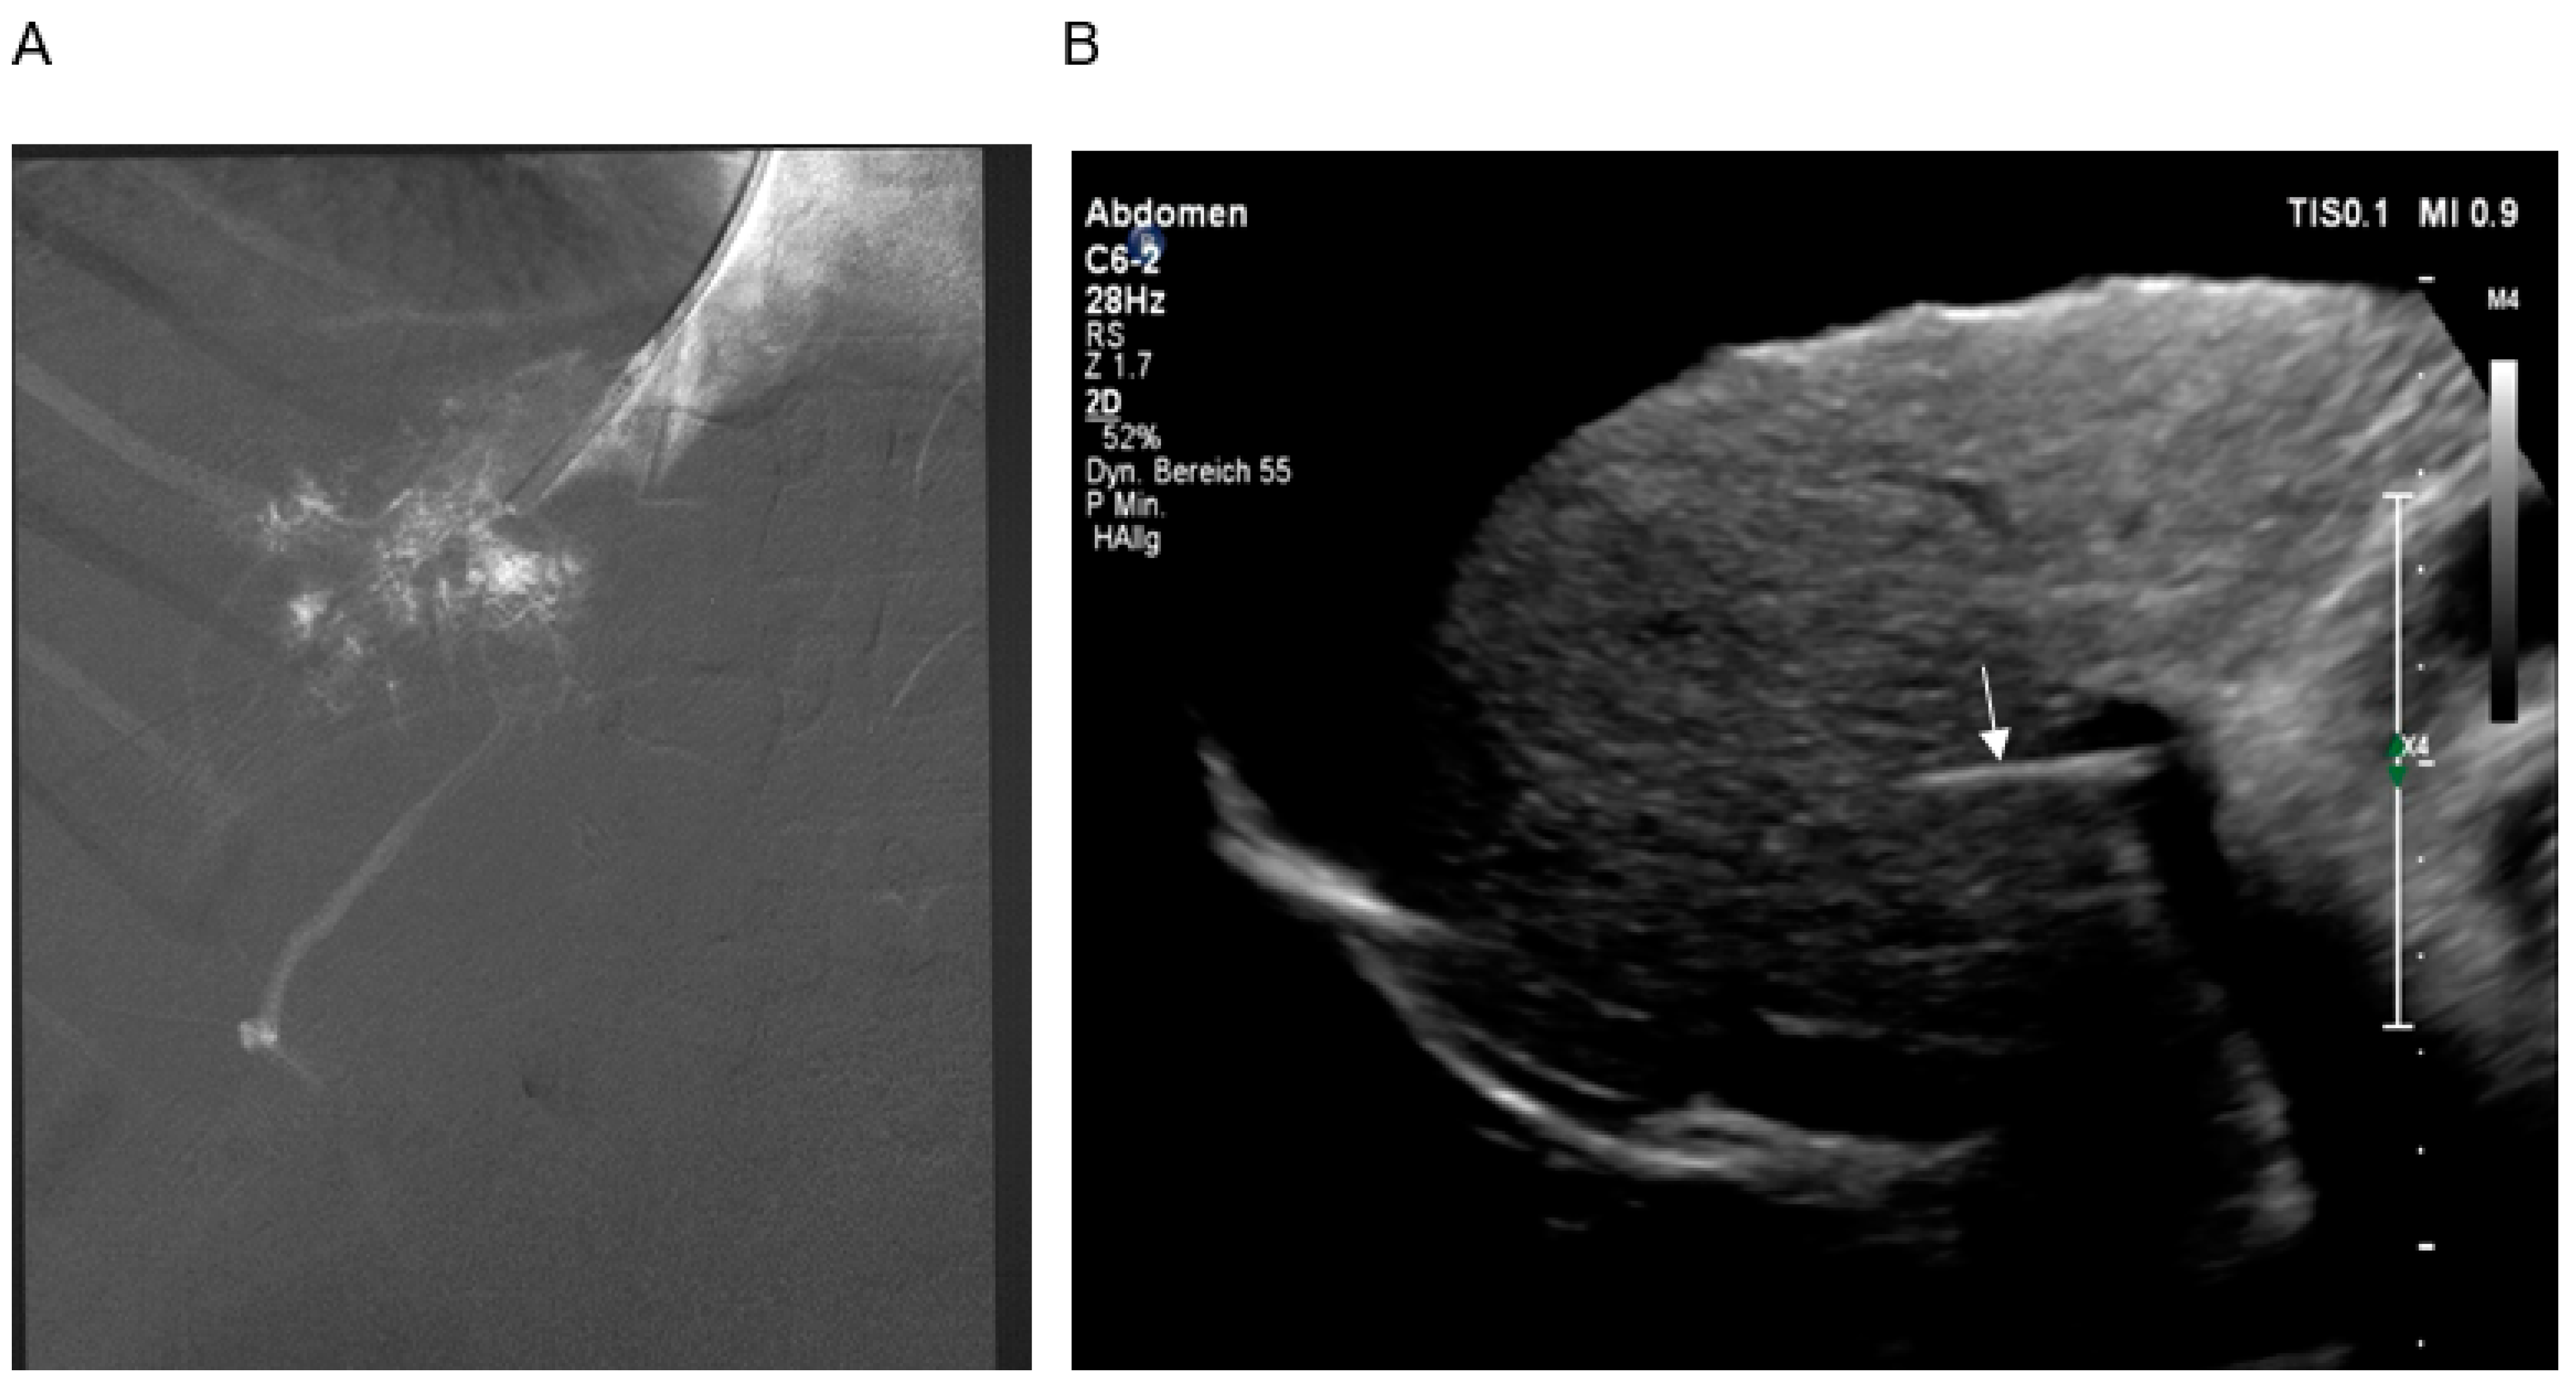

2.2. TIPS

2.2.2. Technique of TIPS Implantation